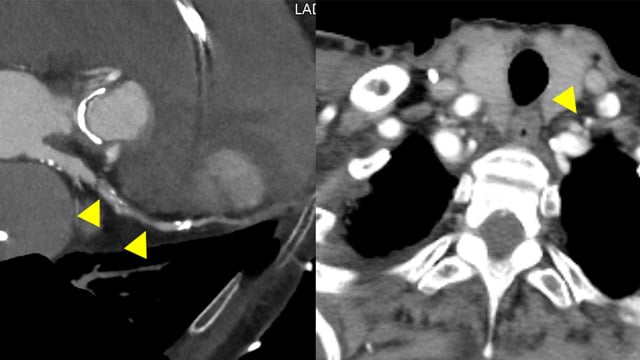

This session explores complex coronary challenges and anatomical anomalies encountered in clinical practice. Topics include management of thrombus showers from unexpected culprits, ultra-low contrast angioplasty in mesenteric ischemia, advanced bifurcation PCI techniques with IVUS guidance, and troubleshooting difficult stent delivery scenarios in calcified lesions and challenging...